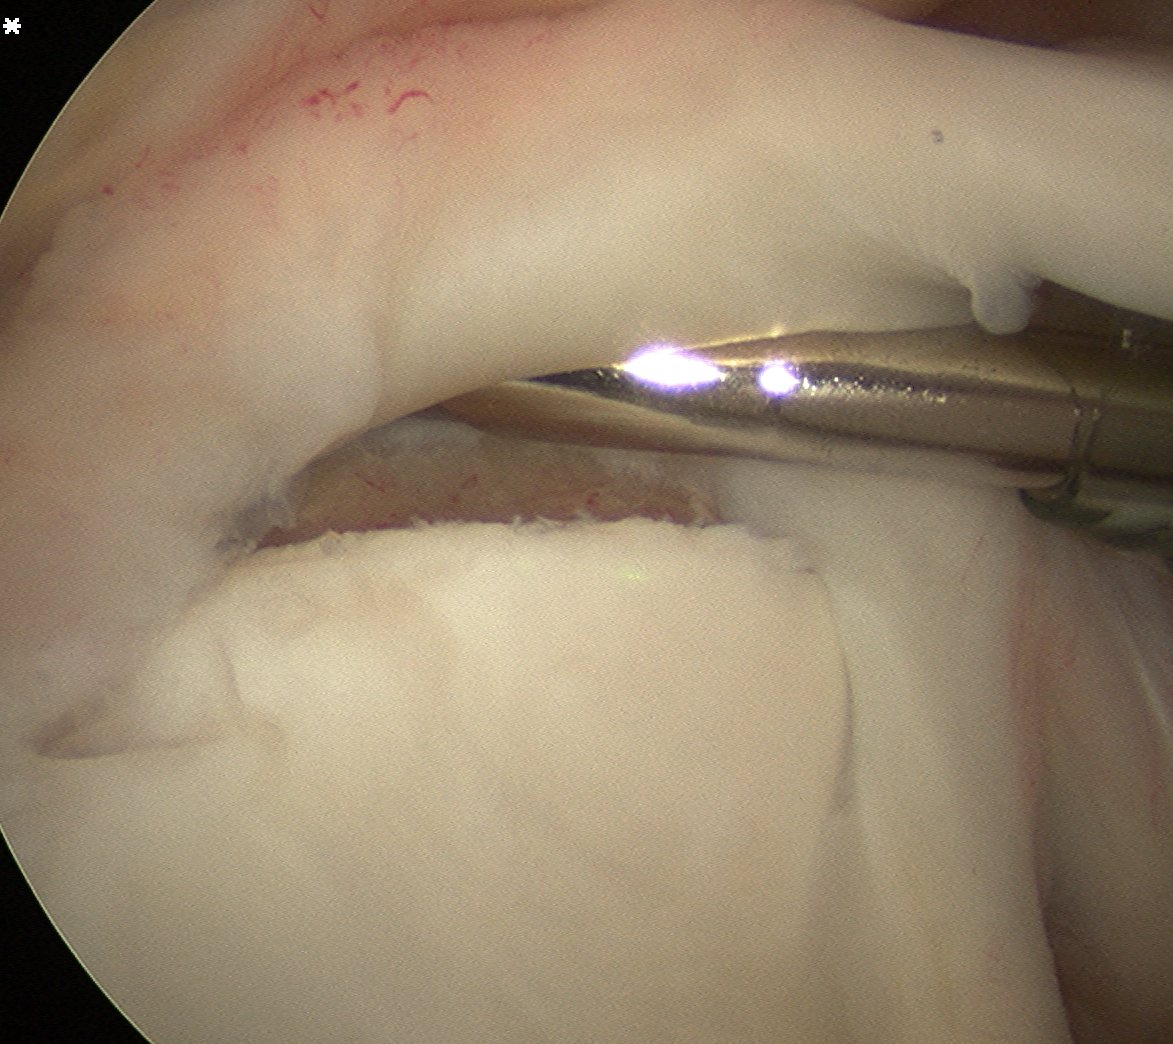

2. Prepare insertion

- shaver via anterior portal

- debride frayed labrum

- mobilise biceps tendon

- debride bony base to create ledge and bleeding bone